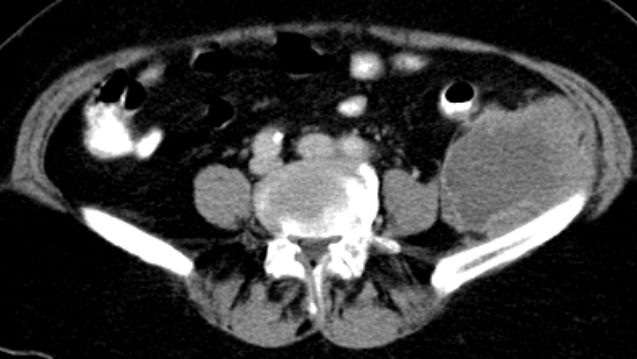

| Diagnostik | partiell nekrotisches, pleomorphes undifferenziertes Sarkom der Bauchwand.![]() |